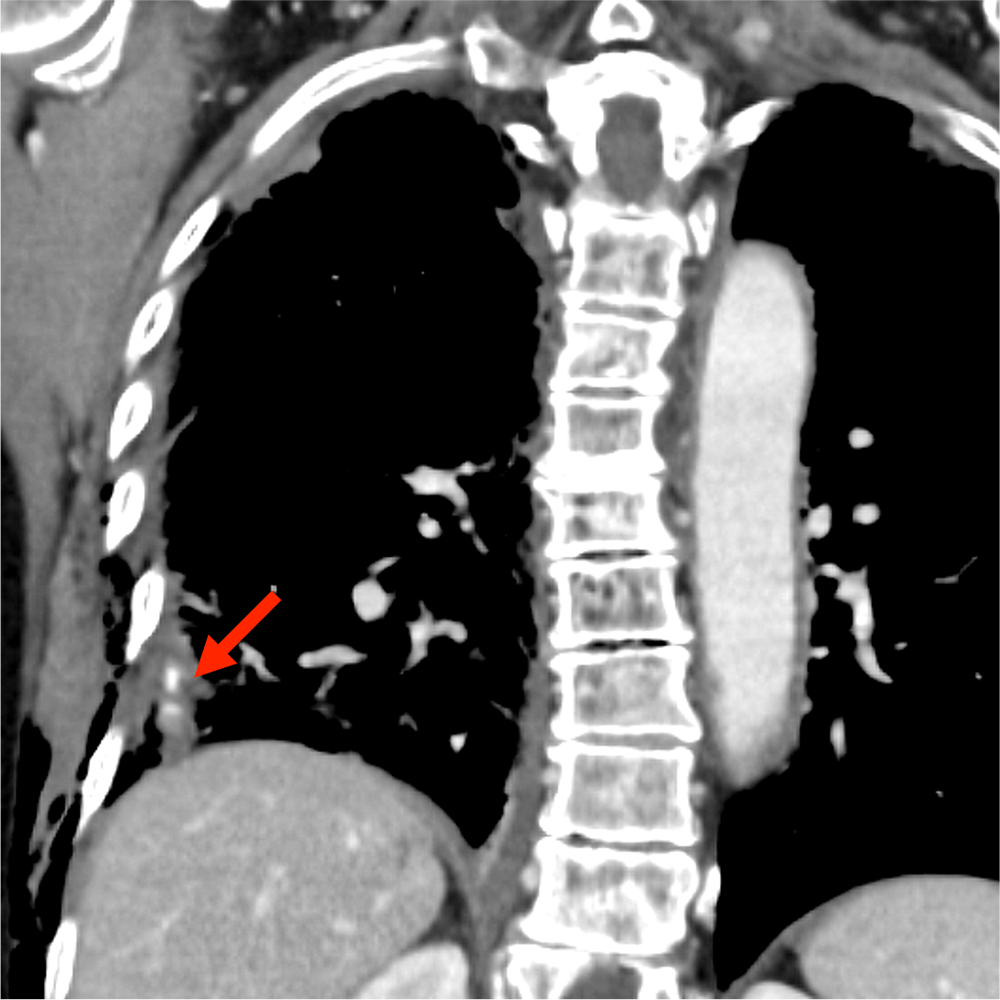

CTでは多発肋骨骨折、外傷性血気胸、肺挫傷、胸壁内気腫が認められた。

挫傷した肺内には結節状構造がみられ、肺気瘤の形成が示唆される。造影CTではこの内部に点状の濃染影が認められ、肺実質内血管外漏出(extravasation in the lung:EVIL)が疑われた。